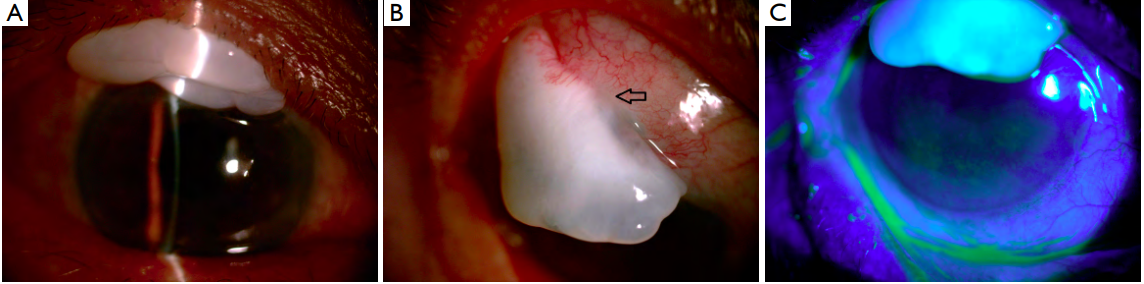

The patient underwent surgical dissection of the

overhanging bleb and scar tissues on the cornea. Leakage of

aqueous could be seen from the base of the bleb. Revision

of the bleb using superior conjunctival flap was performed.

Histopathologic evaluation showed proliferation of fibrous

tissue under the conjunctival epithelia with irregular

cystoids change (Figure 3A,B).

On the first post-operative day, BCVA was 20/40 and IOP was 15 mmHg. The bleb was flat and diffuse (Figure 4A). Six months later, BCVA increased to 20/25, while the IOP was stable and the bleb was functioning well (Figure 4B,C).

(A). The bleb was wellmaintained six months after surgery (B) without leakage (C).

Figure 3 Histopathologic evaluation showed proliferation of ff brous tissue under the conjunctival epithelia (A) with irregular cystoids (B).

Figure 4 Post-operative slit-lamp examination.